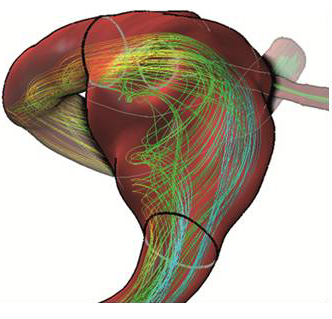

The downside of the Marching Cubes algorithm, however, is that it only operates with a fixed intensity threshold across the entire data set. Since typically a point spread function with a radius greater than one has to be assumed for most imaging techniques, this may cause errors in the boundary geometry, overestimating larger vessels and underestimating smaller vessels. Gradient-based approaches can achieve better results in these cases identifying the location where the maximal gradient value is assumed to find a more accurate estimate for the exact location of the vessel boundary Wischgoll:2008 . The geometric model resulting from the segmentation step can then be further refined, for example by using smoothing or rounding off the transitions at vessel bifurcations Oeltze:2005 , resulting in a vessel boundary that can be used for a CFD simulation. Figure 1(a) shows an example of such a vessel boundary generated based on a CT scan using gradient-based thresholding with sub-voxel precision.

2.2 Computational Fluid Dynamics Model

In addition to the geometric boundary of the vascular structure inflow, outflow, and wall boundary conditions have to be defined properly for the CFD simulation Cebral2005 ; Venugopal2007 . Inflow and outflow conditions arise from the fact that the current vascular structure has to be isolated from the rest of the arterial system. In practice, the flow rate or the speed profile at the inlets and the pressure at the outlets are utilized for a cardiac cycle. These quantities are obtained based on experimental measurements or by time-resolved Phase-contrast MRI flow measuring from the patient (see subsequent section). boundary condition arises from the fact that the vessel wall is distensible, which may influence the local hemodynamic and vice versa Torii2009 . However, typically no proper characterization of the arterial wall, such as modulus of elasticity, wall thickness, or pressure wave that form at the wall, is available or is difficult to measure noninvasively Cebral2005 . Thus, a rigid wall is assumed in most cases, which also decreases the numerical computation time. With all boundary conditions defined, the flow can be computed based on the 3D unsteady Navier-Stokes equations for an incompressible Newtonian fluid. Typically, common CFD solvers are used for this step, for example ANSYS Fluent or OpenFOAM. The resulting velocity and pressure of the blood flow can subsequently be used for further analysis. For example, the computation of the dimensionless Reynolds number Cebral2009 . The Reynolds (Re) number characterizes the local flow behaviour in terms of laminar (Re ) or turbulent (Re ). In addition to velocity and pressure values, other hemodynamic quantities are obtained during the simulation. An important quantity is the wall shear stress (WSS), which represents the tangential force produced by blood moving across the vessel surface. It is known that WSS has an influence on the tissue structure of the vessel wall and it is likely that WSS plays an important role in initiation, growth and rupture of cerebral aneurysms Nixon2010 . The WSS can be computed based on the velocity field and the geometry Huo:2009 ; Cebral2009 . Figure 1(b) shows the result of such a CFD simulation using the inlet pressure and velocity based on a typical heart rate. This simulation is based on 124 time steps. For each time step, a grid size of 500,000 cells was used to accurately represent the vascular structure resulting in close to 900MB of data. CFD simulations give blood flow information at high resolution. However, CFD simulations are based on models with assumptions and simplifications which make it difficult to obtain patient-specific accurate results.